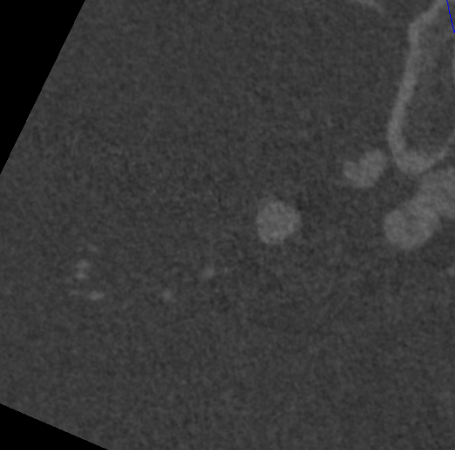

右侧颈总造影:右侧大脑中动脉瘤

右侧大脑中动脉瘤,瘤颈处发出颞支,颈宽3.79mm,瘤高3.51mm,远近端载瘤动脉直径分别为2.43mm、2.52mm。